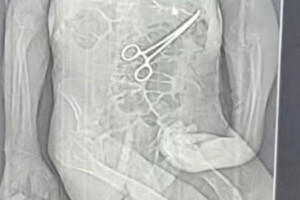

Homem morre na véspera do Natal e família diz que pinça foi deixada em seu corpo após cirurgia